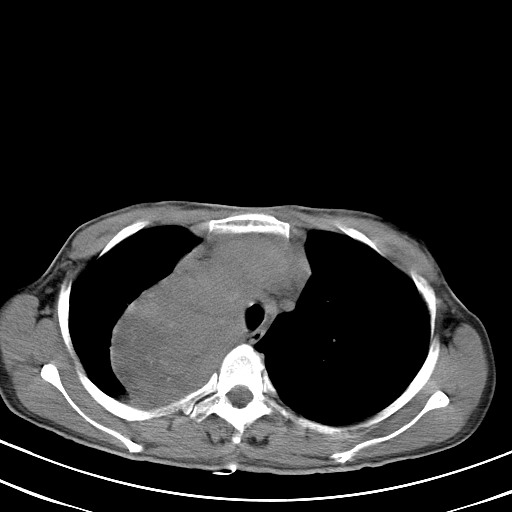

以下是引用汪涛同志在2007-8-2 0:40:00的发言:[br]病变虽然广泛,同时侵及双侧纵隔,但是无论左侧和右侧上下观察都是与右侧颈部甲状腺相延续的,而且强化幅度基本一致,又同时具有恶性病变病变的某些特征:肿块过大且密度不均,部分层面与正常纵隔结构分界不清,结合病史已有两年,考虑:胸内甲状腺肿恶变可能。[br]